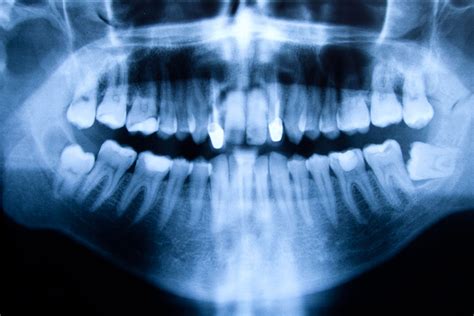

Ante la presencia de los síntomas antes descritos, se debe recurrir a un profesional de la salud dental para que determine cuál es el diagnóstico correcto. Generalmente los quistes dentales se observan a través de una radiografía panorámica o una radiografía 3D que es mucho más precisa y exacta. Estos estudios determinarán el tamaño del quiste, su origen, la posición, el estado del diente y de la encía y cómo afecta a los dientes cercanos a él.

Durante la revisión, el odontólogo puede detectar signos indirectos como la presencia de una fístula o la inflamación de la zona periapical. Sin embargo, la confirmación de la presencia de un quiste radicular se obtiene mediante imágenes radiográficas como las radiografías periapicales, las ortopantomografías (visión panorámica de ambos maxilares) o las tomografías computarizada de haz cónico (CBCT).